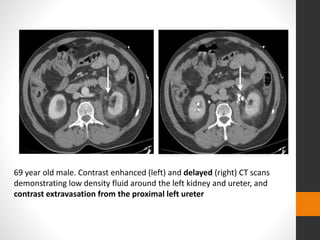

69 year old male. Contrast enhanced (left) and delayed (right) CT scans

demonstrating low density fluid around the left kidney and ureter, and

contrast extravasation from the proximal left ureter